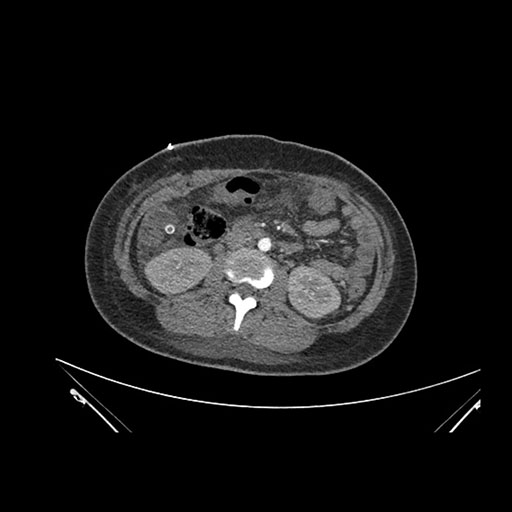

Imaging Analysis

Look through the patient's CT scan to identify any areas of concern for the necessary procedure.

Axial Arterial